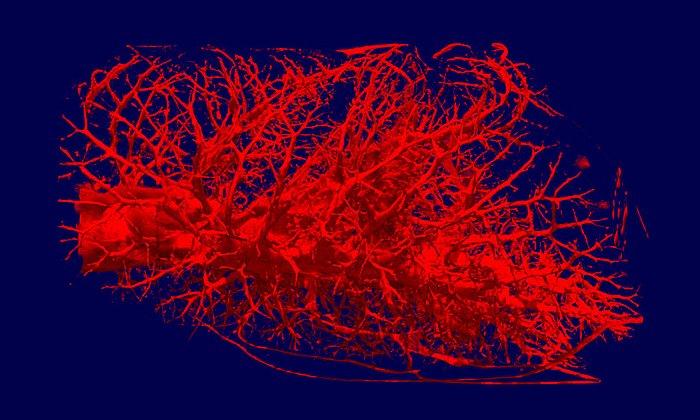

Seine Ergebnisse erstaunen: Nur bei den Proben eines depressiven Patienten, der mit Lithium behandelt worden war, beobachtete Josef Lichtinger eine höhere Anreicherung des Lithium in der sogenannten weißen Substanz. Das ist der Bereich im menschlichen Gehirn, in dem die Nervenbahnen laufen. Der Lithiumgehalt in der benachbarten grauen Substanz war 3-4-fach geringer. Die Lithium-Anreicherung in der weißen Substanz konnte bei mehreren unbehandelten depressiven Patienten dagegen nicht beobachtet werden. Das weist darauf hin, dass Lithium nicht wie andere Psychopharmaka im Zwischenraum der Nervenzellen wirkt, sondern in den Nervenbahnen selbst.

Nun will Josef Lichtinger weitere Gewebeproben an der Forschungs-Neutronenquelle in Garching untersuchen, um seine Ergebnisse zu bestätigen und zu erweitern. Am Ende des Projekts steht eine Landkarte des Gehirns eines gesunden und eines depressiven Patienten, die ortsaufgelöst die Lithiumanreicherung zeigt. So könnte man das Universalmedikament Lithium zukünftig noch zielgenauer und kontrollierter gegen psychische Erkrankungen einsetzen. Die Arbeit wird von der Deutschen Forschungsgemeinschaft (DFG) unterstützt.